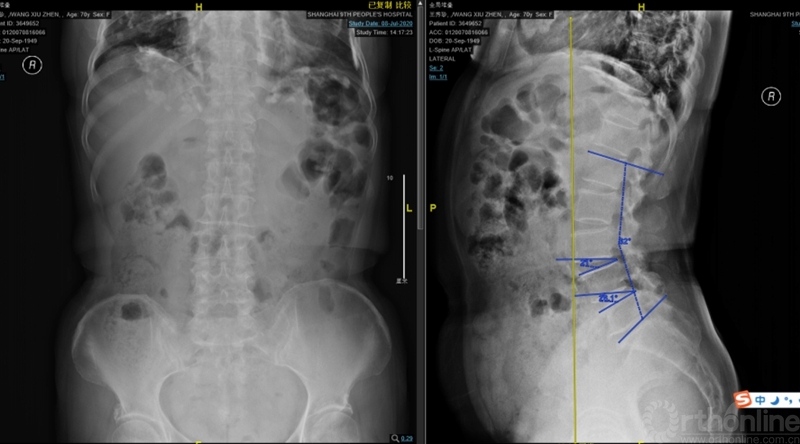

本文提供一例病例,高PI的腰椎显著前凸多节段的腰椎管狭窄症合并腰椎滑脱的患者(PI:57度,LL: 62度,图1、2、3),术前影像显示腰3-4、4-5椎管狭窄、椎体滑脱(图2、3),术前临床表现为右侧下肢麻木无力症状,术中接受了双节段MIS-TLIF手术。

图2:术前腰椎正侧位:腰3-4、4-5滑脱。腰椎矢状面顶椎腰23椎间隙,LL:62°,L34椎间隙与水平成角度21°,L45椎间隙与水平成角26°,椎间隙方向为术中工作通道方向。

图3:术前核磁:腰3-4、4-5椎管狭窄